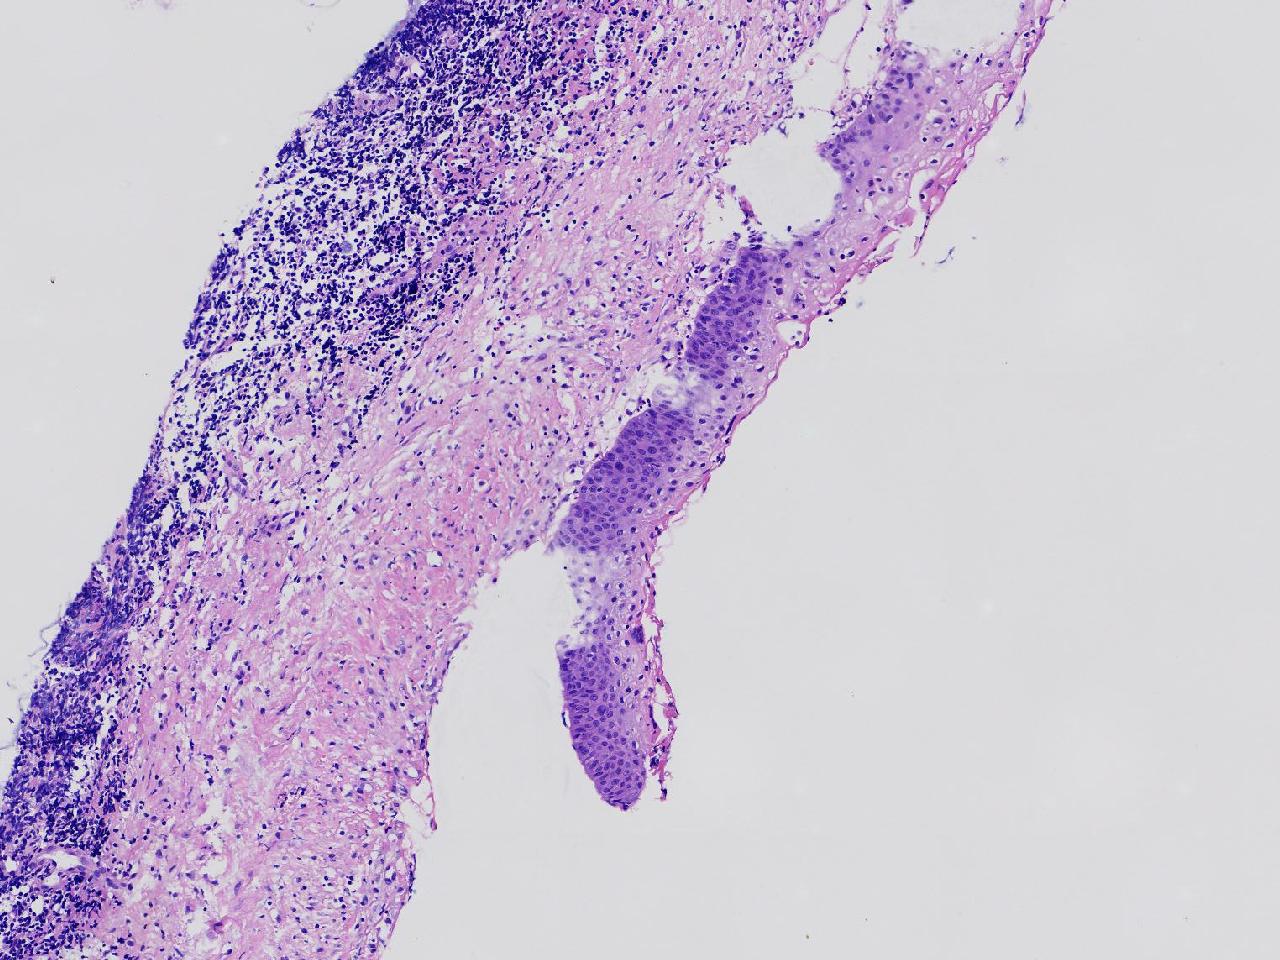

女,59岁,宫颈活检,TCT报告ASC—US, HPV不详。

宫颈多点活检。

灰白色不整形软组织多块。

图1

CIN1,建议HPV检测

高级别